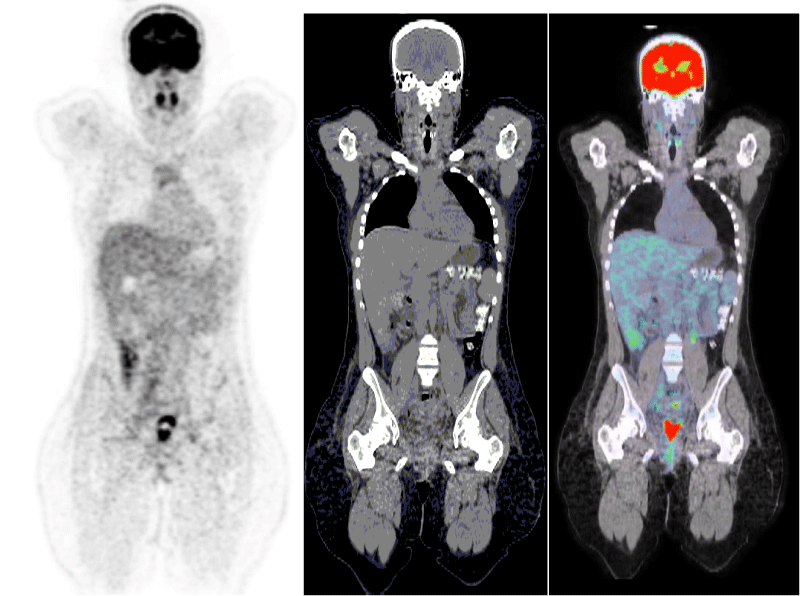

Post-operatively, an 18-fluorodeoxyglucose positron emission tomography (FDG-PET) scan, was performed in order to establish the full initial extension status of this aggressive tumour. It showed no sign of metastasis or remaining disease (Figure 4).

Figure 4: Pet-scan 3 days after the operation showing no sign of distant metastasis of the ovarian carcinoma.